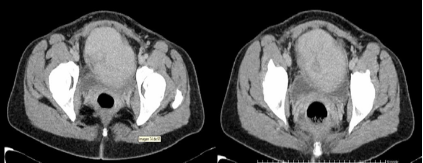

Tomografía axial computarizada abdominal, simple y con contraste: Las imágenes revelaron una gran lesión tumoral en la excavación pélvica de 9,8 x 8,6 x 7,4 cm, con densidad variable de entre 20-60 UH, que comprimía la vejiga y se proyectaba en la porción anterior de la pelvis (no dependía del útero) hacia la línea media y por delante de la vejiga. El sistema excretor renal no se encontraba dilatado y no existían lesiones hepáticas hipercaptantes, óseas, lumbares ni pélvicas (fig. 1 y fig. 2).

Fig. 2. Tomografía axial computarizada simple y con contraste (vista de un corte de la neoplasia)